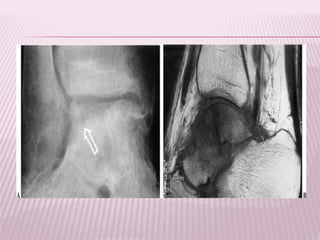

FRACTURA SUBCAPITAL

 Aquellas producidas en un plano

inmediatamente inferior al borde del cartílago

articular, generalmente tiene una orientación

oblicua de modo que compromete un

segmento pequeño de cuello del fémur.